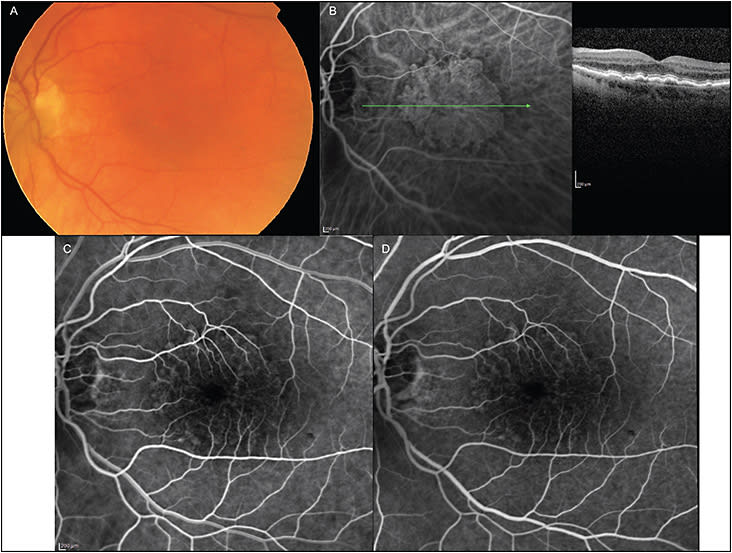

Interestingly, the existence of MNV in eyes without overt features of neovascularization or exudation was shown on histopathology of postmortem eyes as early as the 1970s.1,2 Subsequently, several large case series have reported abnormal indocyanine green (ICG) findings that are consistent with the presence of nonexudative neovascular complexes.3-5 These studies described the appearance of a late staining plaque in the ICG angiographic frames without any leakage detectable on fluorescein angiography, as shown in Figure 1. Interestingly, some eyes with choroidal neovascularization (CNV) of the occult type that leak on fluorescein angiography can form similar plaques on ICG angiography. These correlations, therefore, suggested that the late staining ICG plaques without leakage into the subretinal space were a form of subretinal pigment epithelial dormant neovascular complex.

In a systematic review by Laiginhas et al,10 12 publications about the use of OCTA in the context of neMNV were reviewed. The prevalence of subclinical nonexudative neovascular AMD in the fellow eyes of patients with unilateral exudative AMD ranged from 6.25% to 27%. The incidence of exudation in these eyes ranged from 20% to 80% (over 6 months to 2 years of follow-up). We illustrate a case of neMNV using OCTA (Figure 2).